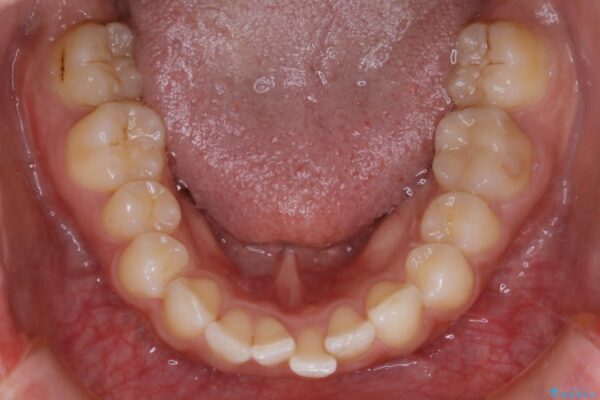

気になるガタツキと噛み合わせを改善したいとご来院されました。

下の歯列よりも上の歯列が前に出ている状態を治すため、マウスピース矯正に加え、患者様にゴムかけのご協力をいただきました。その結果、ガタつきが改善し、上下の噛み合わせが適切な位置で合うようになりました。

歯並びが悪くなる原因の一つに「歯列弓の狭窄」というものがあります。

奥歯や前歯が内側(舌側)に倒れ込んでしまったり、歯が生えてくる位置が内側になってしまうことにより歯並びのアーチが狭くなってしまうことを言います。

このような場合、歯並びのアーチを拡大してあげるだけでもガタつきを無くすためのスペースがかなり作れることがあります。